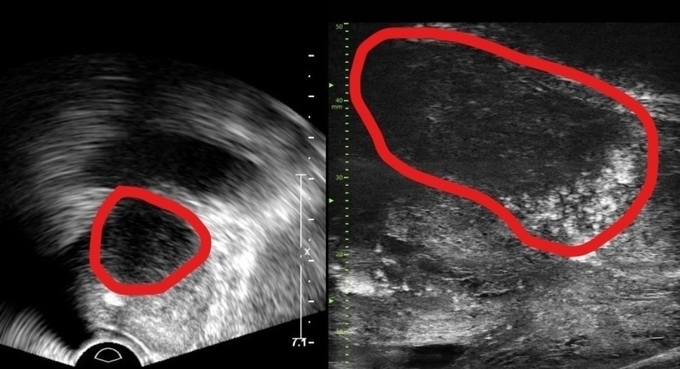

29MHz 마이크로 초음파를 사용하는 이 장비는 전립선과 주변의 해부학적 구조를 선명히 표시하고 표적 조직검사를 유도한다. 의심 영역을 실시간으로 확인하면서 전립선 조직의 미세한 변화와 병변을 식별하고 조직검사 채취를 위한 바늘을 정확한 위치에 삽입할 수 있다는 장점이 있다.

또한, 전립선 암 진단을 위한 초음파 검사 가이드인 PRI-MUS(Prostate Risk Identification Using Micro-Ultrasound) 위험도 식별 시스템과 연계돼있어 전립선암 병변의 악성 가능성 평가는 물론, 어느 부분에서 조직을 채취해야 하는지 정확히 판단할 수 있게 한다. PRI-MUS는 초음파 상 병변의 모양이나 크기를 자동으로 판단해 병변의 악성도를 1~5단계(높을수록 위험)로 분류하기 때문에 불필요한 조직검사를 줄이면서도 암을 놓치지 않게 돕는다.

기존의 경직장 초음파는 해상도가 낮아 전립선 종양, 특히 작은 암 병변을 감지하는 데 한계가 있었다. 하지만 마이크로 초음파의 높은 해상도와 실시간 영상의 시각화는 자기공명영상(MRI)으로 발견할 수 없는 전립선암을 찾을 때도 충분히 기여할 것으로 기대하고 있다. MRI 검사 보다 환자의 신체적, 심리적, 경제적 부담도 적을 수밖에 없다.